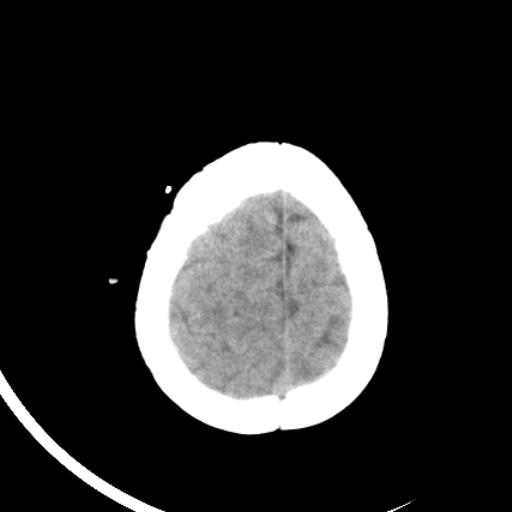

双侧脑室前后角周围白质片状低密度影,双侧侧脑室旁、双顶叶皮层及皮层下多个小原点状钙化灶,不除外torch感染。右顶叶脑回似乎较对侧大,建议mri检查以除外脑发育异常。

考虑:1、巨脑回畸形(皮质明显增厚+脑回明显增宽+白质减少)。

2、torch综合征(室管膜下钙化+白质内及皮髓质交界处多发钙化)。

结节性硬化并无脑回畸形,左侧枕顶叶不排除血管畸形。